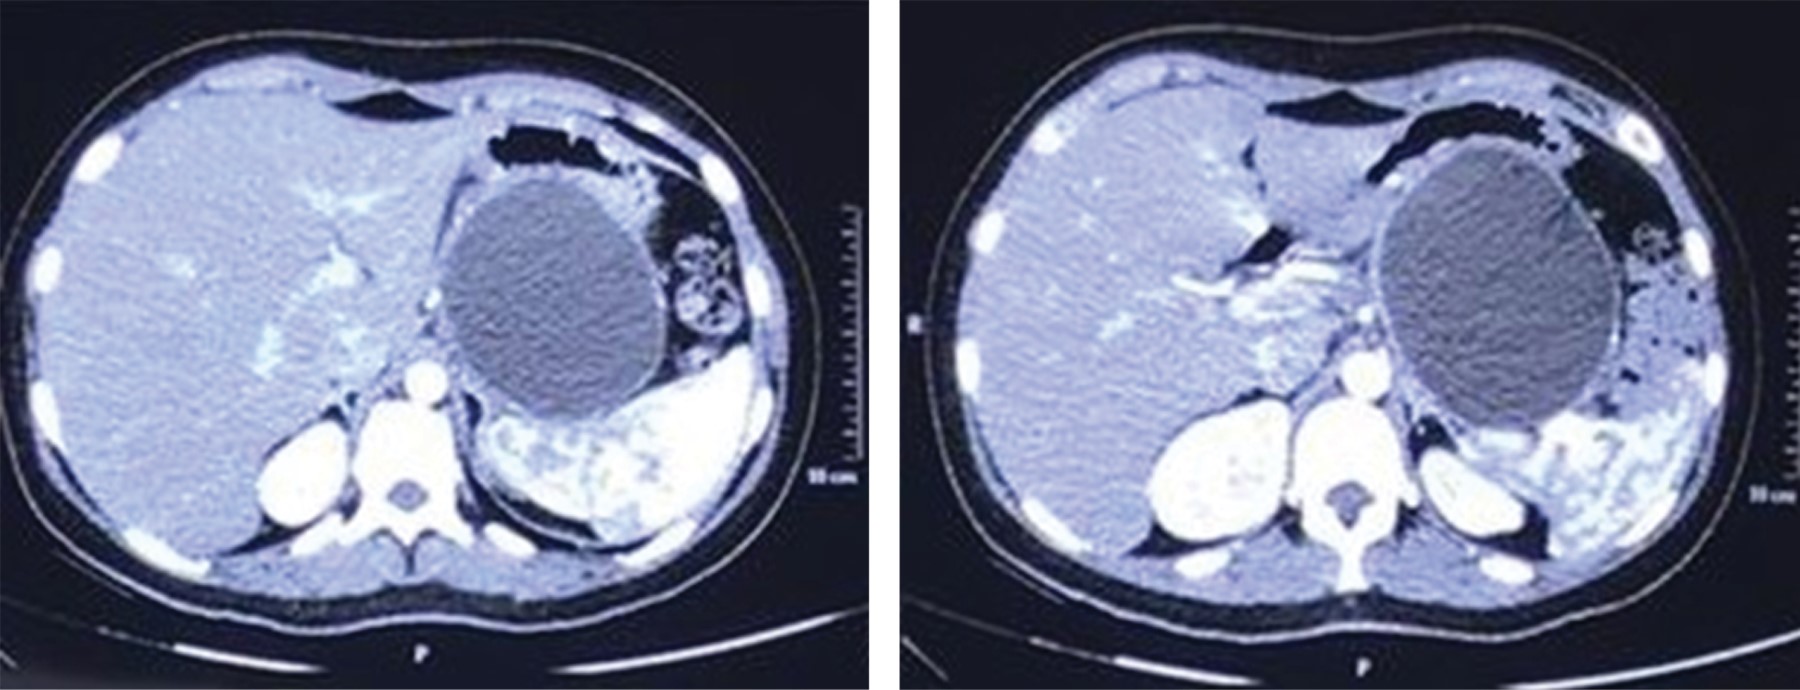

La tomografía de abdomen contrastada muestra páncreas en situación normal, con presencia de lesión quística dependiente de cuerpo y cola, con dimensiones de 105 × 90 mm, de contenido homogéneo, sin captación de medio de contraste, clasificándose como pseudoquiste (Figura 1).

Figura 1